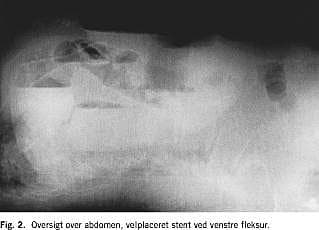

En 87-årig kvinde med kendt tidligere transitorisk cerebral iskæmi og velbehandlet myksødem blev henvist af egen læge til koloskopi pga. ca. et år varende tendens til træg afføring og anæmi. Ved koloskopien fandt man ca. 90 cm fra anus en malignt udseende stenotisk proces. En colonindhældning viste totalt stop ved venstre fleksur ( Fig. 1 ), supplerende undersøgelser viste ingen tegn på metastaser. Der blev anlagt selvekspanderende metalstent under gennemlysning. Der var umiddelbart efter proceduren luft- og fæcesafgang, og en kontrolrøntgen viste velekspanderet stent i det stenotiske colonsegment (Fig. 2 ). Seks dage efter blev der foretaget elektiv laparoskopisk venstresidig hemikolektomi og primær anastomose. Man fandt en tumor i venstre fleksur. Det postoperative forløb var ukompliceret, og patienten kunne udskrives i velbefindende og med tarmfunktion den syvende postoperative dag. En histologisk undersøgelse viste Dukes C adenokarcinom. En kontrolkoloskopi for clean colon viste normale forhold. Ved klinisk kontrol efter et år var patienten velbefindende, uden tegn på recidiv eller metastaser.